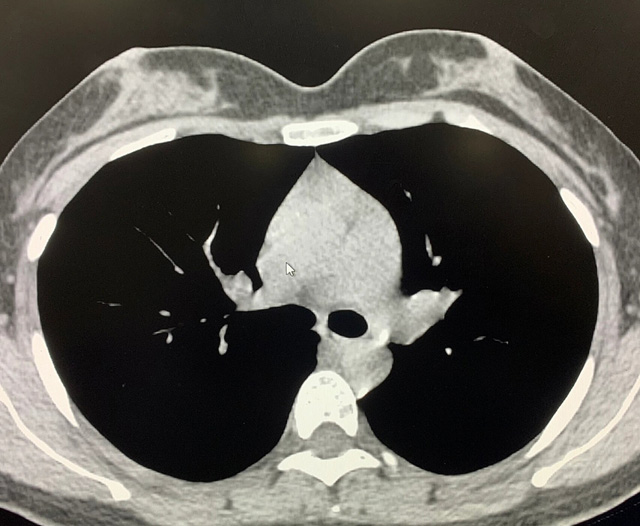

能谱纯化技术CT低剂量胸部扫描

能谱纯化技术的核心是通过物理滤过(如锡滤片)或软件算法,选择性滤除低能X射线光子,保留高能光子。在胸部低剂量CT扫描中显著提升了图像质量与辐射剂量的平衡。

2.明显提高图像质量,高能光子穿透力强,光子通量更均匀,图像噪声(标准差)可降低20%-40%。

3.能谱纯化技术相比于低千伏低剂量技术,可以有效消除线性硬化伪影,提高诊断效能;

优势辐射剂量显著降低相较于常规CT,辐射剂量减少约70%-90%,尤其适合需多次随访的高危人群(如肺癌筛查),降低辐射相关癌症风险早期肺癌筛查效果明确可清晰检测毫米级肺结节,显著提高早期肺癌检出率,降低死亡率。检查快捷且普及性高单次扫描仅需数秒,无需对比剂,设备广泛配置于基层医院,便于大规模筛查。长期成本效益显著虽单次费用与常规CT相近,但早期干预可大幅降低晚期治疗费用及社会医疗负担。技术优化提升图像质量迭代重建算法(如ASIR、MBIR)在降低剂量同时减少噪声,平衡影像质量与安全性。